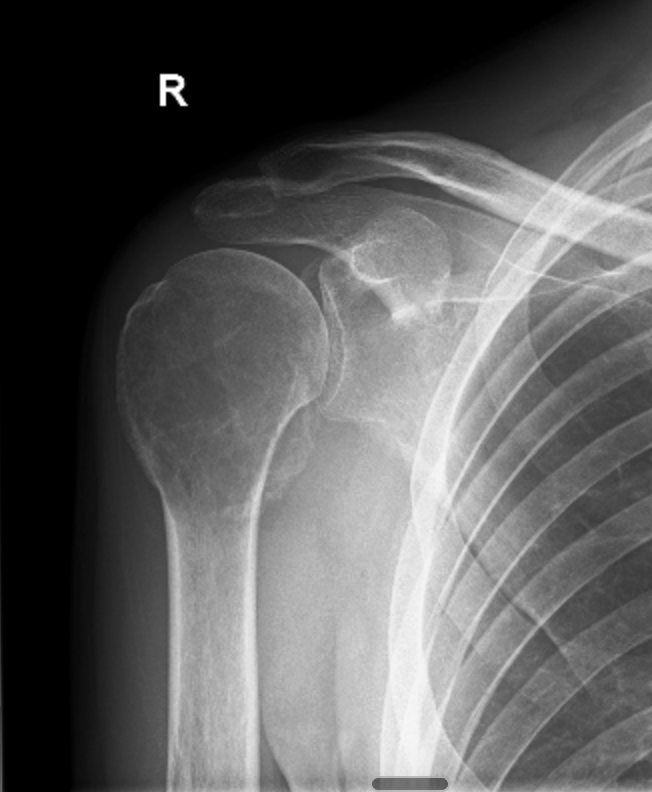

X-ray showing giant cell tumour in the right proximal humerus

X-ray at diagnosis

Then, in early December, I was woken in the middle of the night by excruciating pain. We were living regionally at the time, so it took a few weeks to get an MRI. That scan happened on the 21st of December 2021. Two days later, two days before Christmas, I sat in a room and was told I had a giant cell tumour of bone in my right proximal humerus.

Giant cell tumour of bone, or GCTB, is a rare bone tumour that affects roughly one to two people per million. It's locally aggressive, has a high recurrence rate, and the treatment options are limited: surgery, or a drug called denosumab. That's essentially it.

I was 31 years old, and I'd just been told my shoulder was being eaten from the inside.